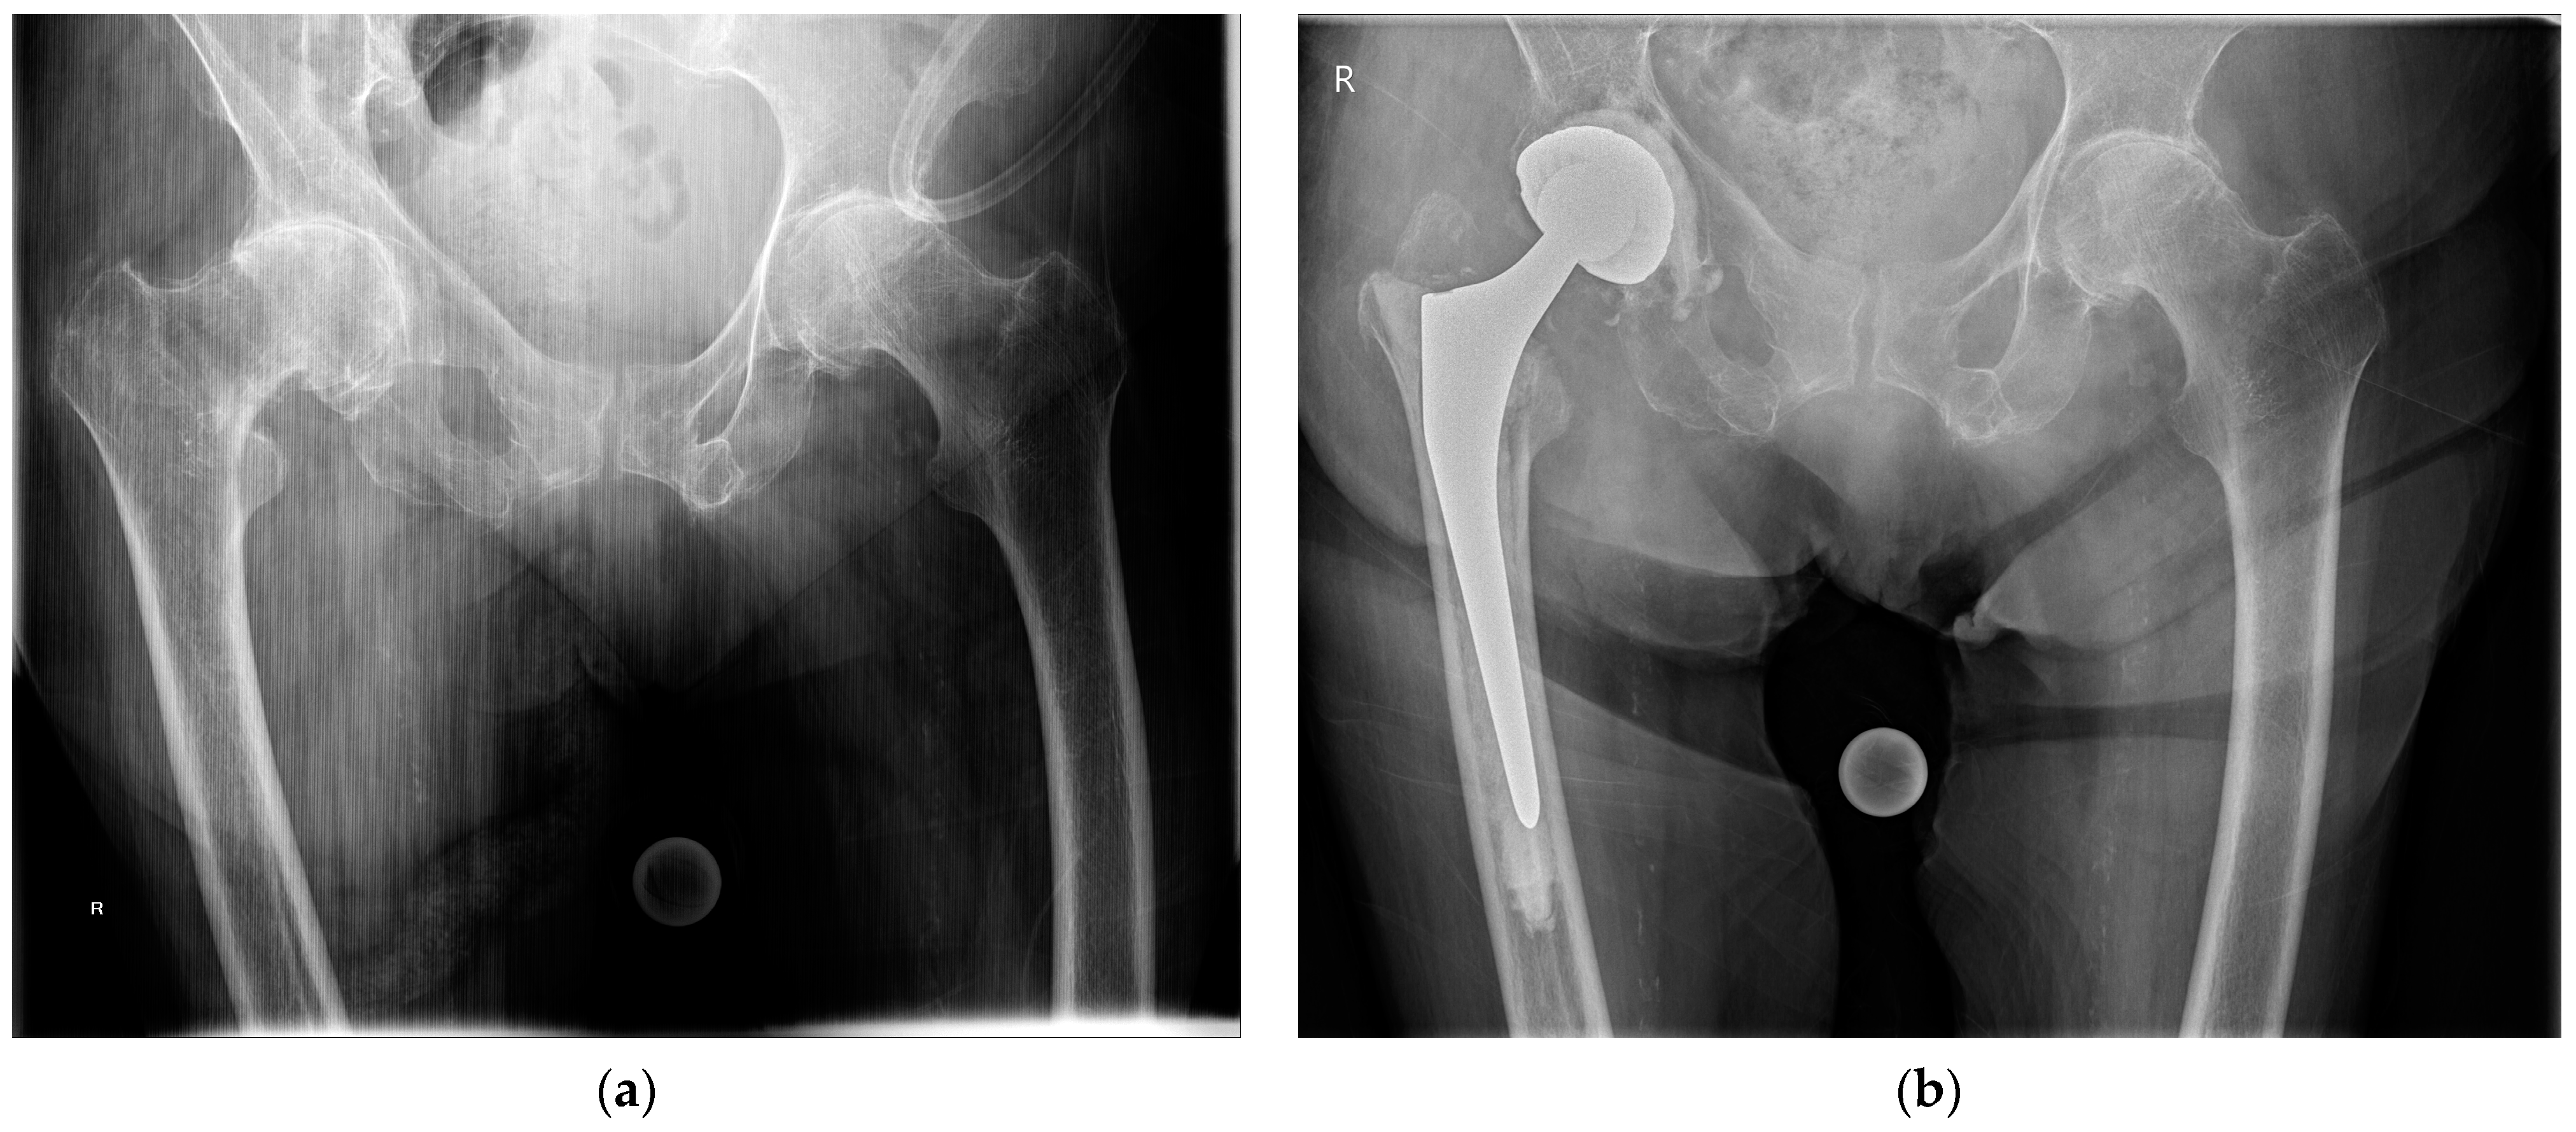

2. Indications

3.2. Implant Selection